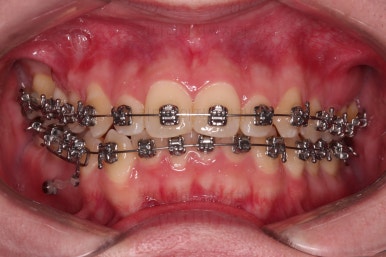

이제 전후 비교를 해볼게요.

1년 7개월 만에 매우 고난이도의 치료를 임플란트 없이 사랑니까지 당겨와서 사용한 만족스러운 치료였습니다.

우측의 결손치아보다 뒤쪽에 있는 치아는 크기나 모양이 원래의 큰 어금니보다 작고 다르게 생겨서 100% 이상적인 교합을 얻기는 한계가 있었어요.

하지만 임플란트 없이 충분히 가능할 수 있게끔 해주어서 환자분도 매우 만족하는 치료가 되었어요.

뿌리도 남아있었고 골 결손도 심했던터라 뒤쪽 치아들이 잘 움직일 것을 고지해 드렸었지만 다행히 거의 문제 없이 치아가 잘 움직였고요.

대신 해당 치아는 뼈가 약하다는 걸 환자분도 인지하시고 관리를 잘해야되는 부분입니다.